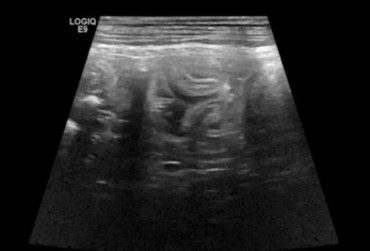

Pies, golden retriever 6mcy. Strunowe ciało obce w jelicie czczym.

24 czerwca 2019

Wojciech Atamaniuk

Czytaj więcej